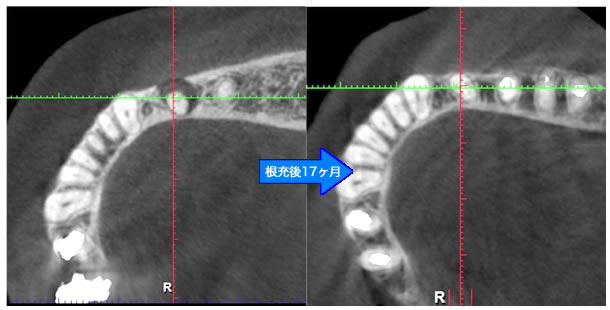

頬側骨の喪失が見られましたが17ヶ月で回復しました。

頬側骨の回復が確認できます。

| 治療説明 | 左下第一小臼歯の頬側根尖部からの排膿、痛みはないそうです。X線画像では根尖部に透過像を認められます。 頬側の骨も失われており、歯髄が死んだことが原因と考えられます。修復物を除去後根管治療を行い、根管充填後、透過像は消失、頬側骨も再生されていました。 |